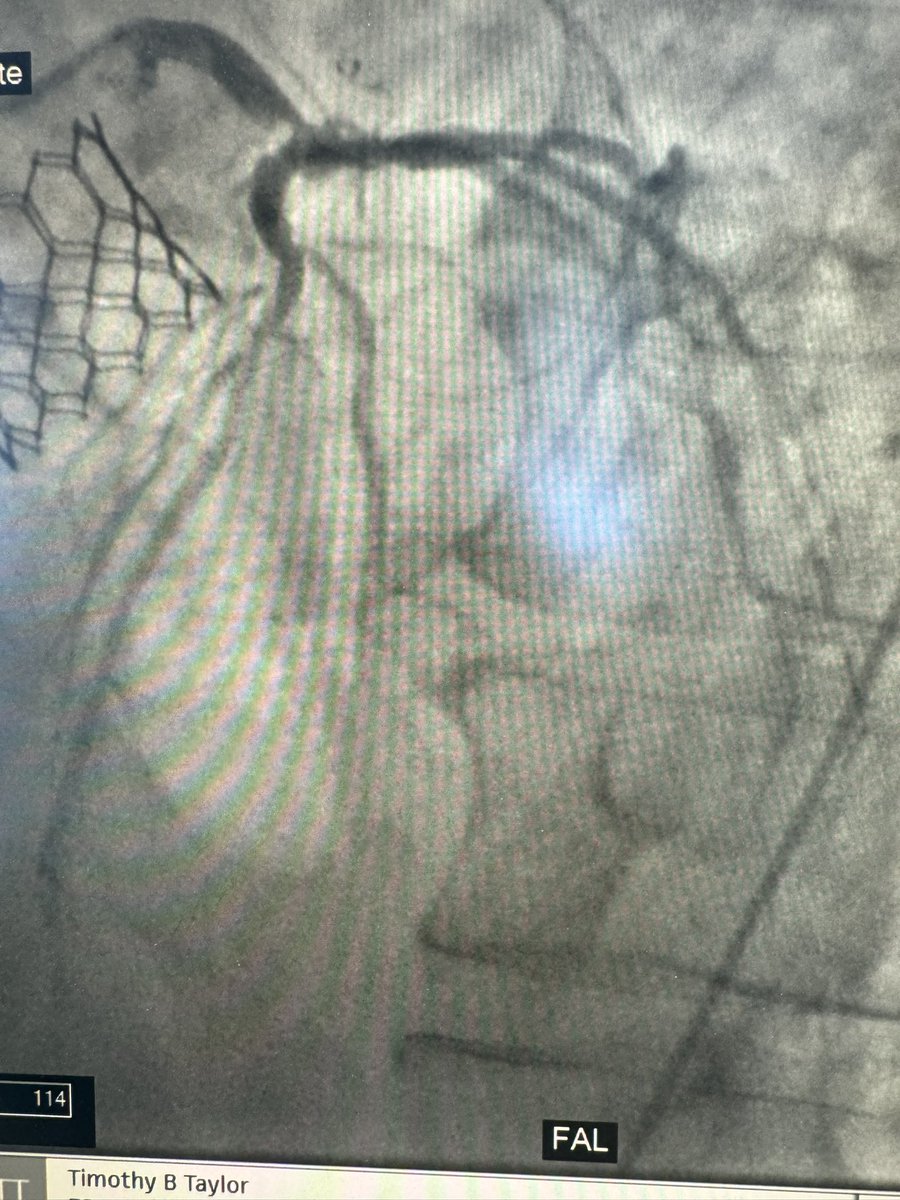

Prior tavr patient comes in 95% left main,hostile cfa’s. U/s guided left axillary and Perc ax impella . CSI to left main single stent to lad plus pots. PTA assisted dry closure with2 preclose w excellent hemostasis. @jcgeorgemd @jaygirimd @DrAmirKaki @JayMathewsMD